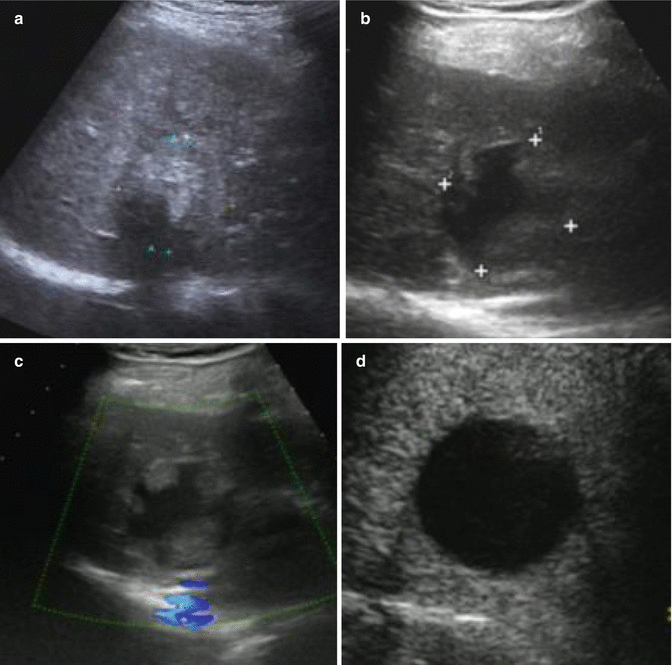

From radiologykey.com

Radiological Assessment and FollowUp After Radiofrequency Ablation Chest Pain Months After Ablation A majority of patients have chest pain for a few days after the procedure. The earliest and most common symptom of acute pericarditis was sharp, pleuritic chest pain after the ablation procedure. Post ablation pericarditis is a type of post cardiac injury syndrome that can be witnessed after radiofrequency or cryoablation procedures for atrial and ventricular. The severity of the. Chest Pain Months After Ablation.